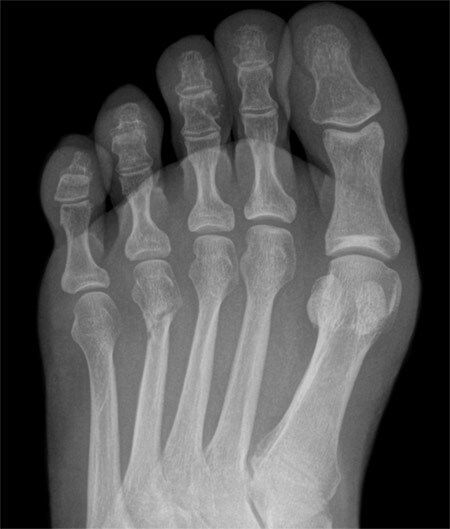

X-RAY QUIZ: Which finding is present on this image?

A: Normal X-ray image

B: Sail sign

C: Meniscus sign

D: Pneumothorax

E: Air bronchogram

Start Quiz bit.ly/36i1txn